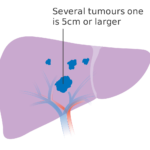

肝臓がん

肝臓がんとは、肝臓に発生するがんの総称です。

腫瘍の発生の形によって「原発性肝がん」「転移性肝がん」の大きく2つに分けられます。